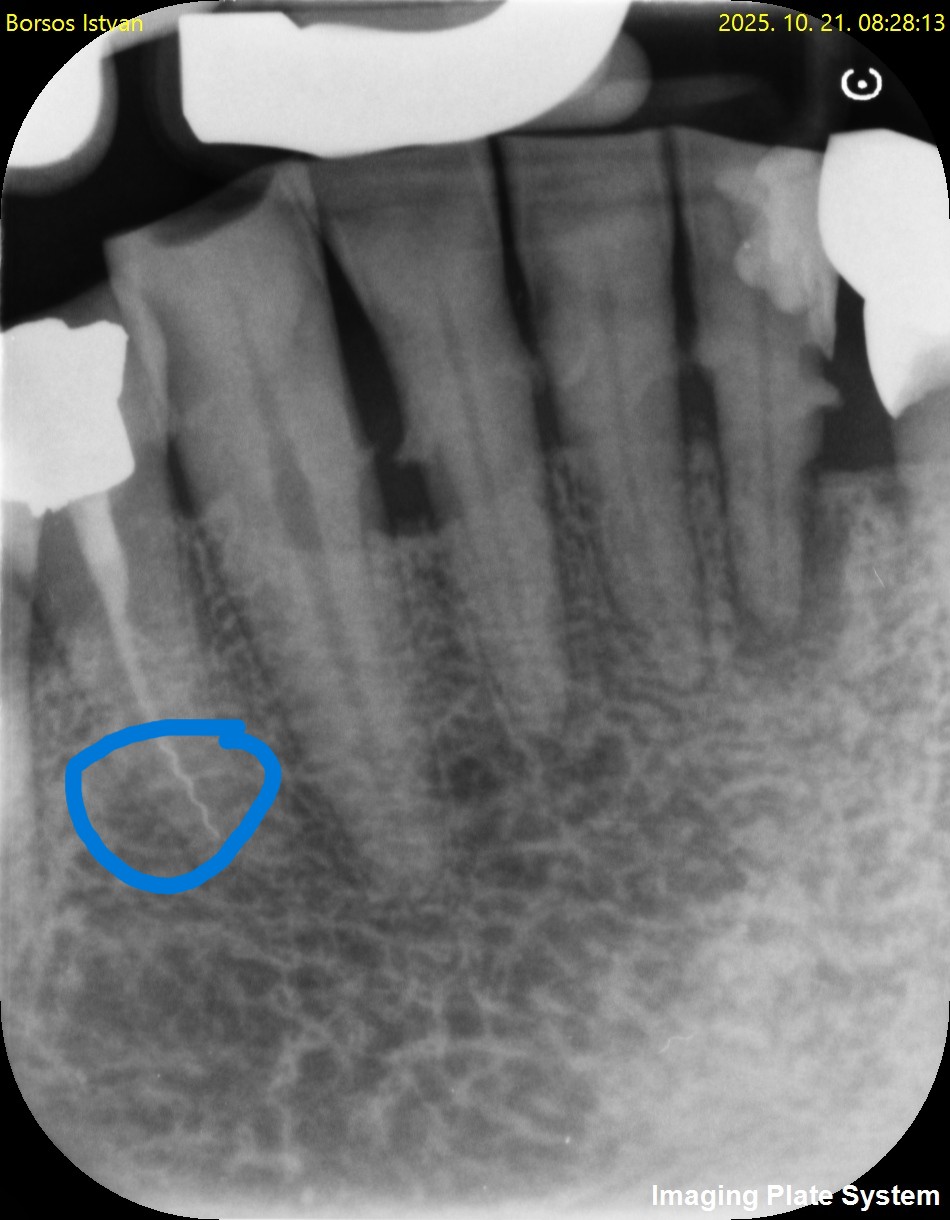

Perforáció (fenti kép)

Tű-törése (fent)

Feltáratlan gyökércsatorna (fent)